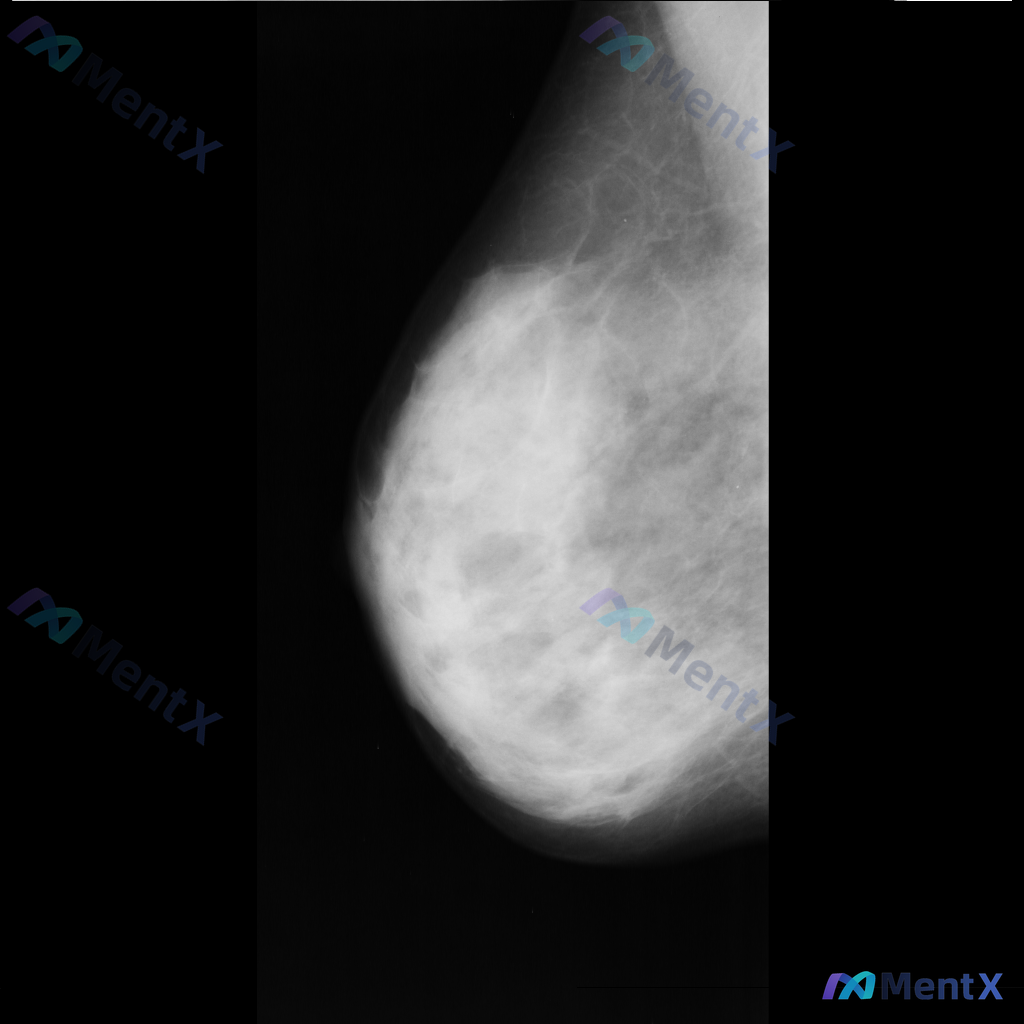

各位老师好,这里有一张乳腺钼靶影像(image: mdb281.png),影像中可见一些异常表现,想请大家一起讨论一下。

整理到一张单侧乳腺钼靶影像的读片资料,目前是单一体位图像,没有双侧对比。 影像表现整理 - 乳腺组织密度较高,属于多量腺体型或致密型背景 - 可见散在的钙化灶:图像中部偏下有数个点状或粗大钙化,形态不规则,但无典型恶性钙化的细小多形性、线样或分支状表现 - 乳腺下象限可见多个高密度圆形/卵圆形影,边...

整理了一份乳腺影像的读片资料,想和大家讨论下判断方向: 基本影像信息 - 单侧乳腺X光片,投照体位考虑可能为内外斜位(MLO) - 乳腺组织构成:不均匀致密型 - 影像质量:曝光适中,清晰度良好,无明显伪影 - 可见结构:皮肤、皮下脂肪层、乳头乳晕、Cooper韧带显示尚可;未见明确钙化血管或腋窝淋...

整理到一张左乳内外斜位(MLO)的钼靶影像资料,先和大家讨论一下读片的情况。 目前已知的信息: - 仅提供了左乳的MLO位单张投照影像 - 影像质量基本良好,基本结构可辨 - 后续补充说明提到患者的乳腺构成类型为不均匀致密型(BI-RADS C) 目前暂时没有更多临床病史、对侧乳腺影像或头足位(CC...